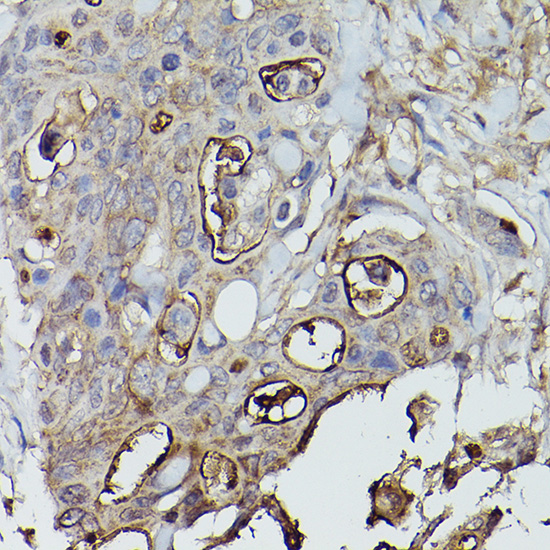

Immunohistochemistry of paraffin-embedded human colon carcinoma using Alkaline Phosphatase (ALPL) Rabbit pAb.

Immunohistochemistry of paraffin-embedded human lung cancer using Alkaline Phosphatase (ALPL) Rabbit pAb.